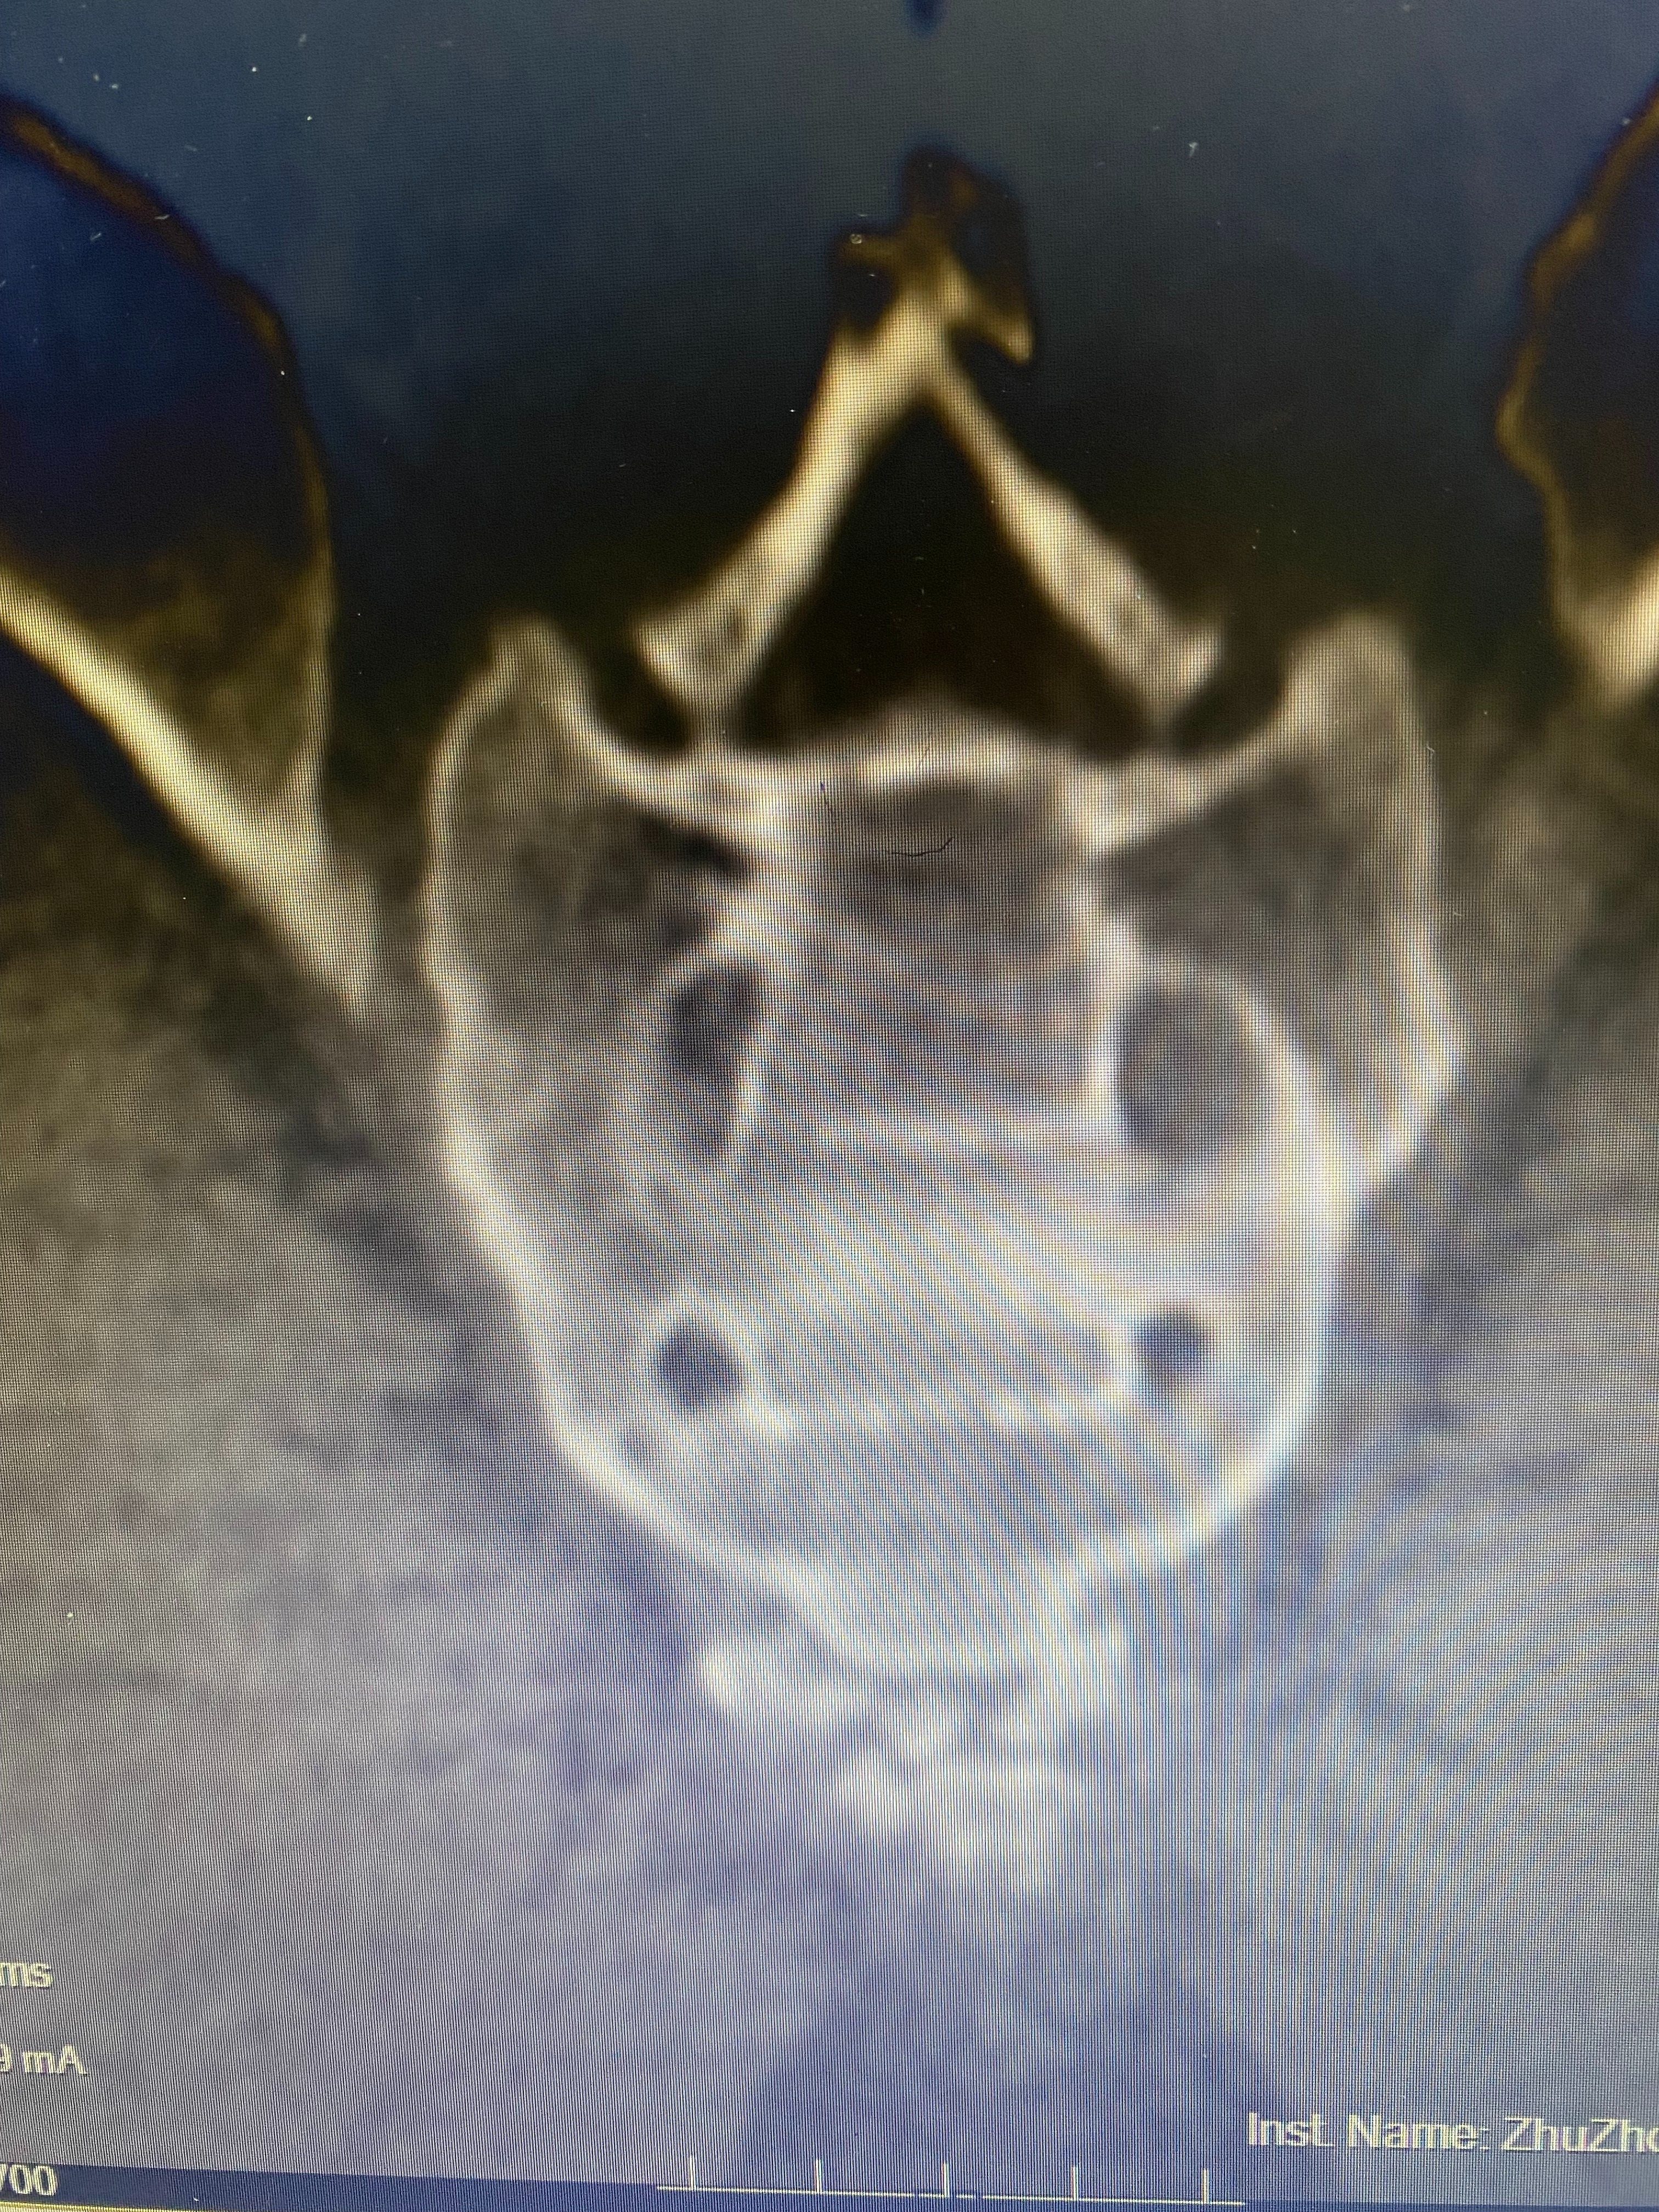

什么是尾骨?杨勋波介绍,尾骨其实就是我们的“小尾巴”,由我们的祖先猿类进化而来,随着人类的进化,尾骨也逐步退化。它略呈三角形,位于肛门后方皮下,由3至4块小骨融合成一大整块,并在彼此之间有关节存在,是构成盆骨的一部分。